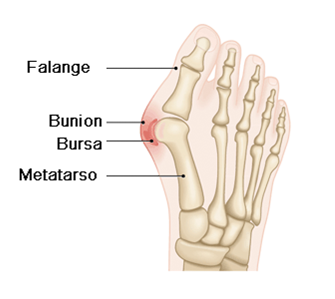

O hallux valgus, também conhecido como joanete, é uma deformidade anatómica que afeta o dedo grande do pé (hallux) e é uma das patologias mais comuns do pé.

É caracterizada pelo desvio do hallux em direção aos outros dedos menores e do primeiro metatarso para dentro, o que provoca uma proeminência óssea na base do primeiro dedo, denominada bunion.